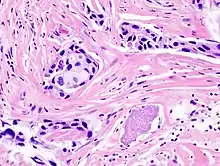

- Histopathology – the microscopic examination of stained tissue sections using histological techniques. The standard stains are haematoxylin and eosin, but many others exist. The use of haematoxylin and eosin-stained slides to provide specific diagnoses based on morphology is considered to be the core skill of anatomic pathology. The science of staining tissues sections is called histochemistry.